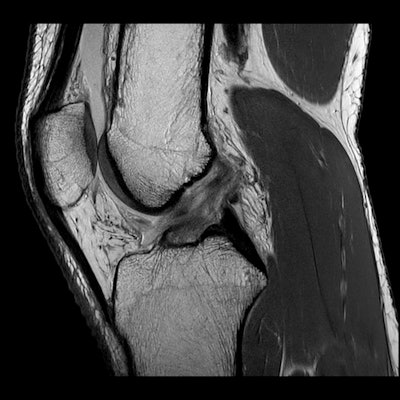

AFL (Australian Football League) football, rugby, and netball account for most injuries -- much more than, say, soccer, basketball, and cricket. As the physical demands of these sports have changed, we see many more muscle injuries (particularly hamstring and calf) than before. In the last five years, we have seen more women transition over to football and rugby. As a consequence, we are seeing many more injuries in the female population than before; these include muscle tears, shoulder dislocations, and anterior cruciate ligament (ACL) rupture. The incidence of ACL rupture in AFL football for women is nine times that of the male population, which is quite worrisome.

As a diagnostic tool, MRI has superseded both ultrasound and radiographs. For example, we typically perform 80 musculoskeletal MRI scans per day but perhaps fewer than 10 radiographs. There is a broad mix of all the joints. We are now quite confident in assessing muscle injuries and providing accurate information about when an athlete might return to play and the risk of a recurring injury. For intervention, fluoroscopy has become redundant, and we would typically perform 50 to 60 interventions per day under ultrasound or CT guidance.